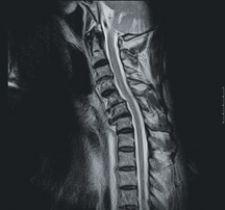

Siemens Medical Solutions has introduced syngo BLADE, the newest Tim (Total imaging matrix) technology-powered MRI software. The technology is capable of imaging in neurological and orthopedic procedures. In cases of severe movement, syngo BLADE motion correction application allows facilities to increase patient throughput and decrease costs.

According to the company, the technology is ideal for pediatric and difficult-to-manage patients in neurological and orthopedic imaging because it is not affected by flow and motion. This application measures and corrects any motion, providing clear images by the continuous acquisition of low-resolution images. With the low sensitivity to movement, it allows medical professionals to focus on reducing sedation rates for pediatric and anxious patients, which in some cases can increase time efficiency.